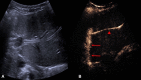

The introduction of ultrasound contrast agents has rendered contrast-enhanced ultrasound (CEUS) a valuable complementary technique to address clinically significant problems. This pictorial review describes the use of CEUS guidance in abdominal intervention and illustrates such application for a range of clinical indications. Clinical application of CEUS discussed include commonly performed abdominal interventional procedures, such as biopsy, drainage, nephrostomy, biliary intervention, abdominal tumor ablation and its subsequent monitoring, and imaging of vascular complications following abdominal intervention. The purpose of this article is to further familiarize readers with the application of CEUS, particularly its specific strength over alternative imaging modalities, in abdominal intervention.